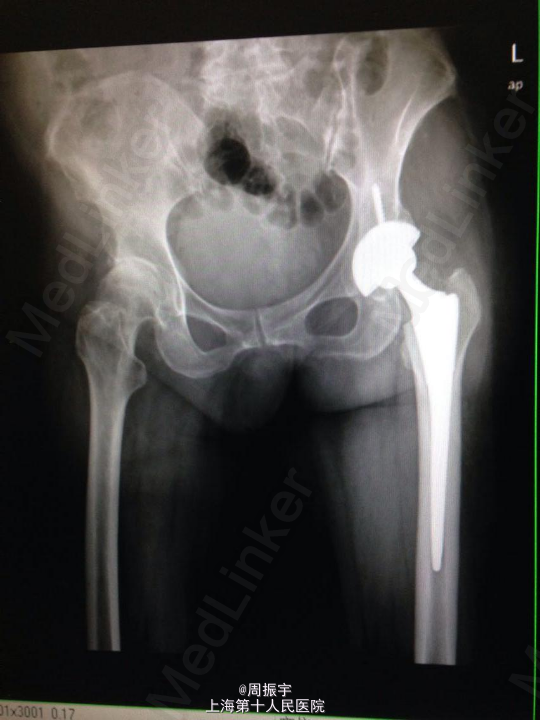

查体:患者发病以来精神可,胃纳差,睡眠差,大小便正常,体重无明显减轻。 左下肢短缩外旋畸形,左髋未见红肿及皮肤破损。左髋压痛(+),左下肢纵向叩击痛(+),足背动脉搏动好。左髋活动明显受限,左膝活动无受限、左踝及足趾活动无异常,左足背动脉搏动好。左下肢较右下肢稍缩短约1cm。余肢体均正常。 辅查:X线:左股骨颈骨折。 骨盆正位数字化摄影 , 检查诊断:左侧人工髋关节置换术后。右髋关节退变,右股骨头坏死可能,请结合临床。

诊断:左股骨颈囊内骨折(Garden IV型) 治疗经过:患者入院后完善各项检查,明确诊断,积极术前准备,全麻下行左侧全髋关节置换术,术顺。